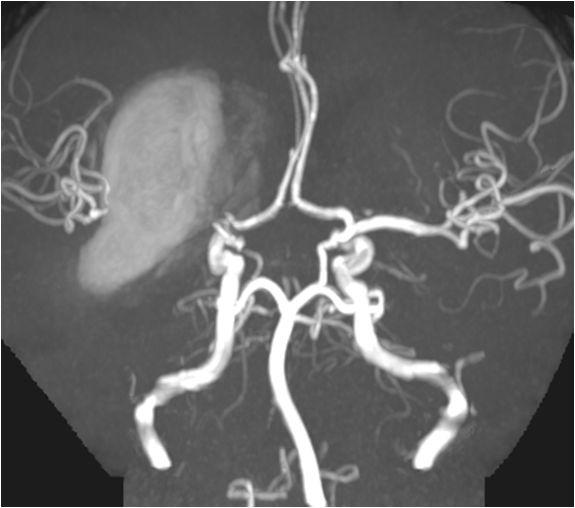

急诊MRA示:基底动脉尖丢失,决定急诊取栓再通。

右侧椎动脉造影:基底动脉中段充盈缺损,基底动脉尖丢失。提示基底动脉中段原位狭窄基础上血栓形成,血栓脱落栓塞基底尖。

微导丝微导管通过闭塞部位,经微导管造影,确认在远端真腔。

一把拉通后,前向血流即刻恢复至3级,双侧小脑上动脉、大脑后动脉、基底动脉尖显影。

现基底动脉残余狭窄约40%,观察20min前向血流3级;斑块累及小脑前下动脉;右侧丘脑出血转化,尽可能避免双抗,综合考虑后放弃急诊支架植入,术后给予盐酸替罗非班泵入维持血流稳定。